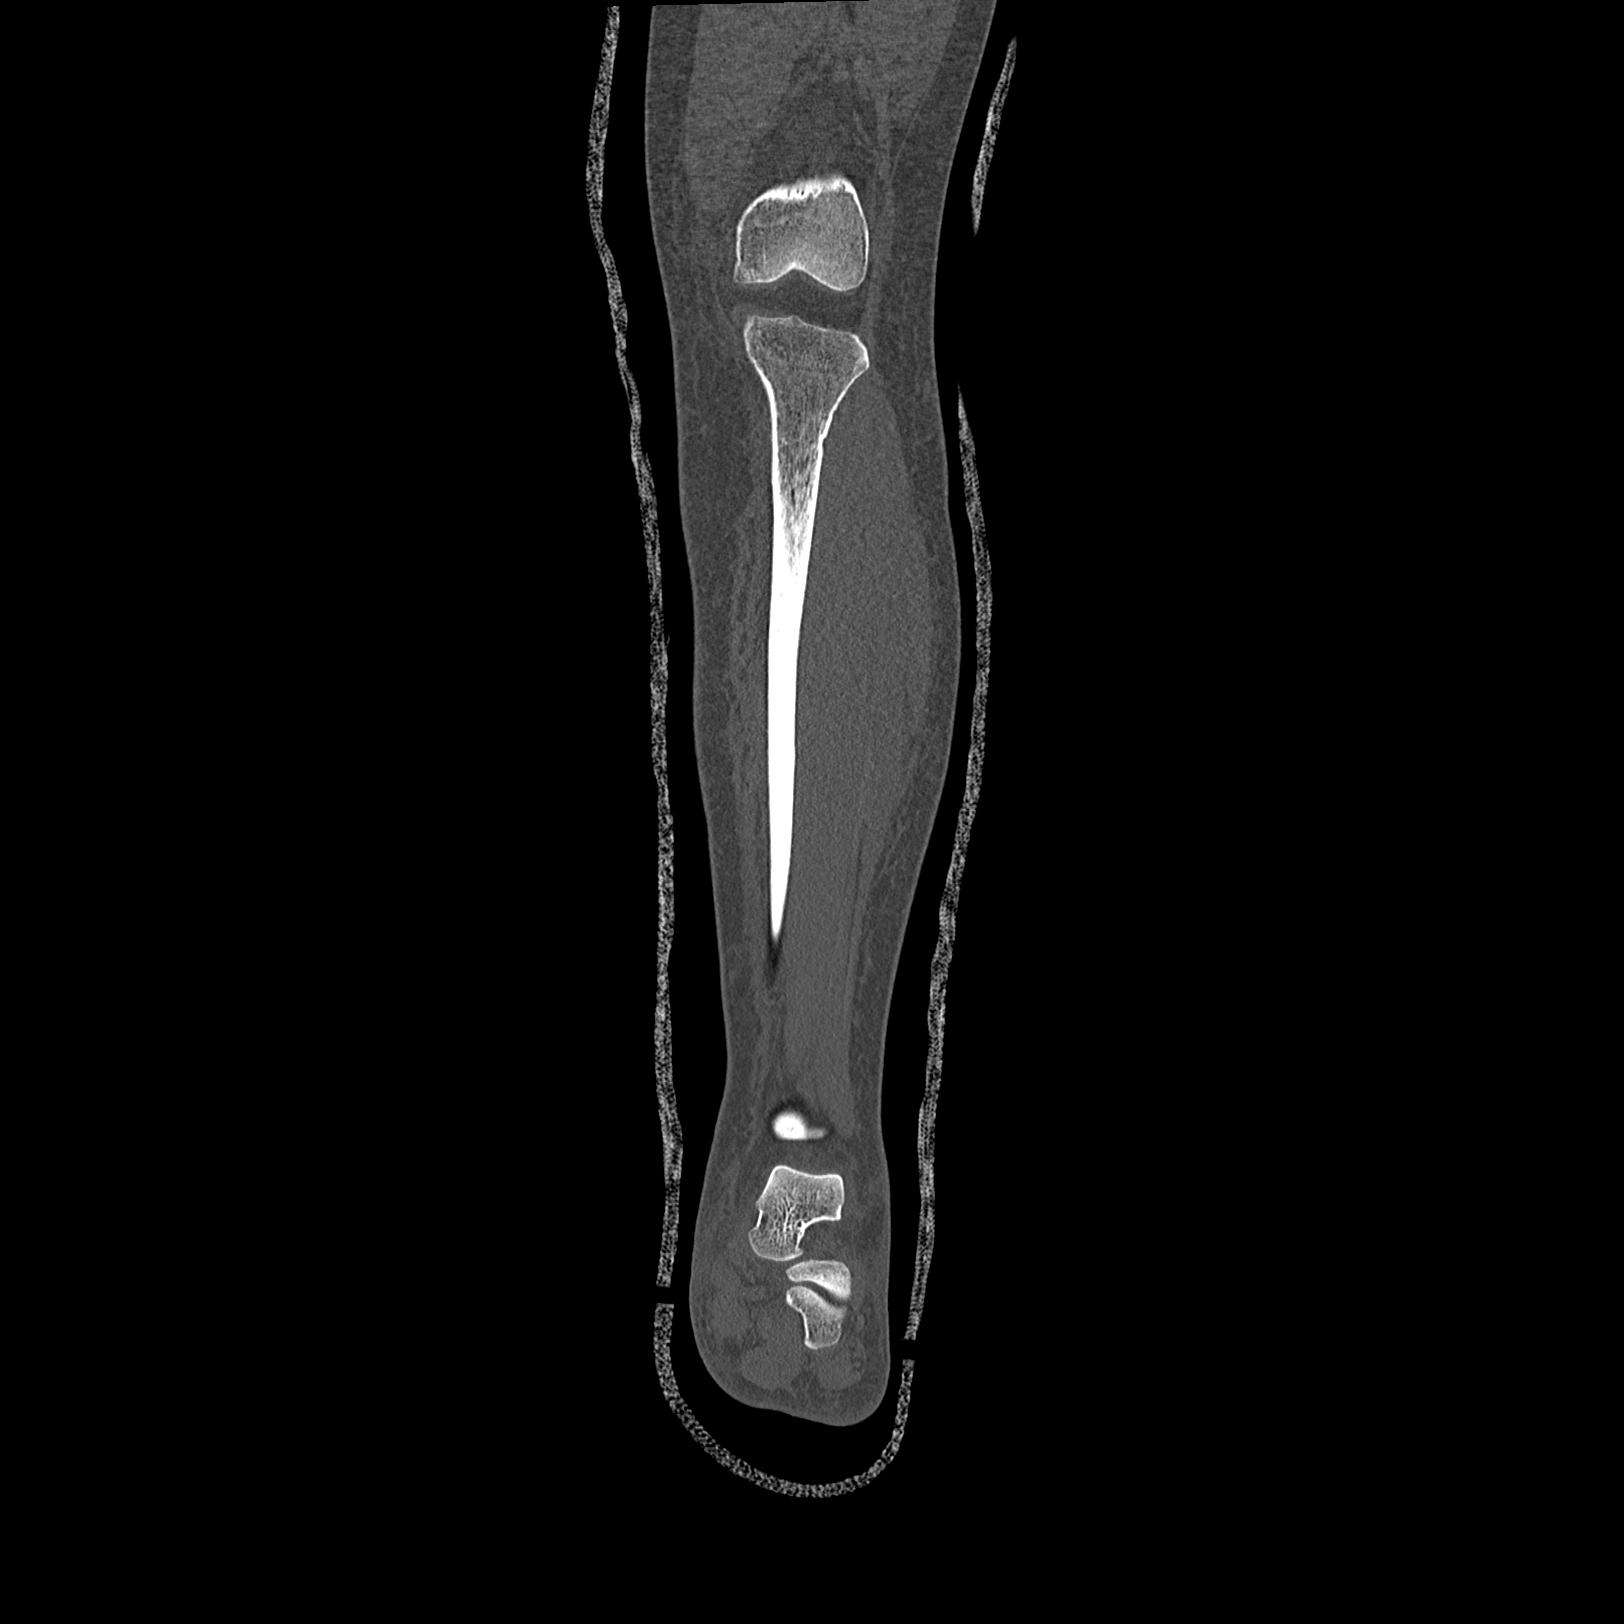

102803 1/12(キウスなし) 1/27 左下腿 4R 30歳女性 左脛骨軸内釘